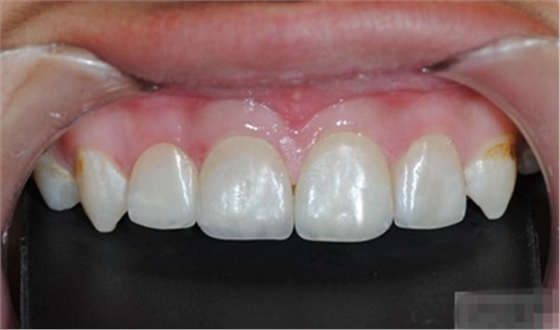

充填初步完成

【初步修整】

修整完成

【充填完成】

1、樹脂貼面平齊牙齦邊緣是最佳設(shè)計(jì),或者使用齦上邊緣 。

2、釉質(zhì)邊緣要用橡皮輪拋光。拋光可以去除懸釉。這樣經(jīng)過車針打磨過的釉質(zhì)表面會(huì)更加均一,形成良好的邊緣封閉。